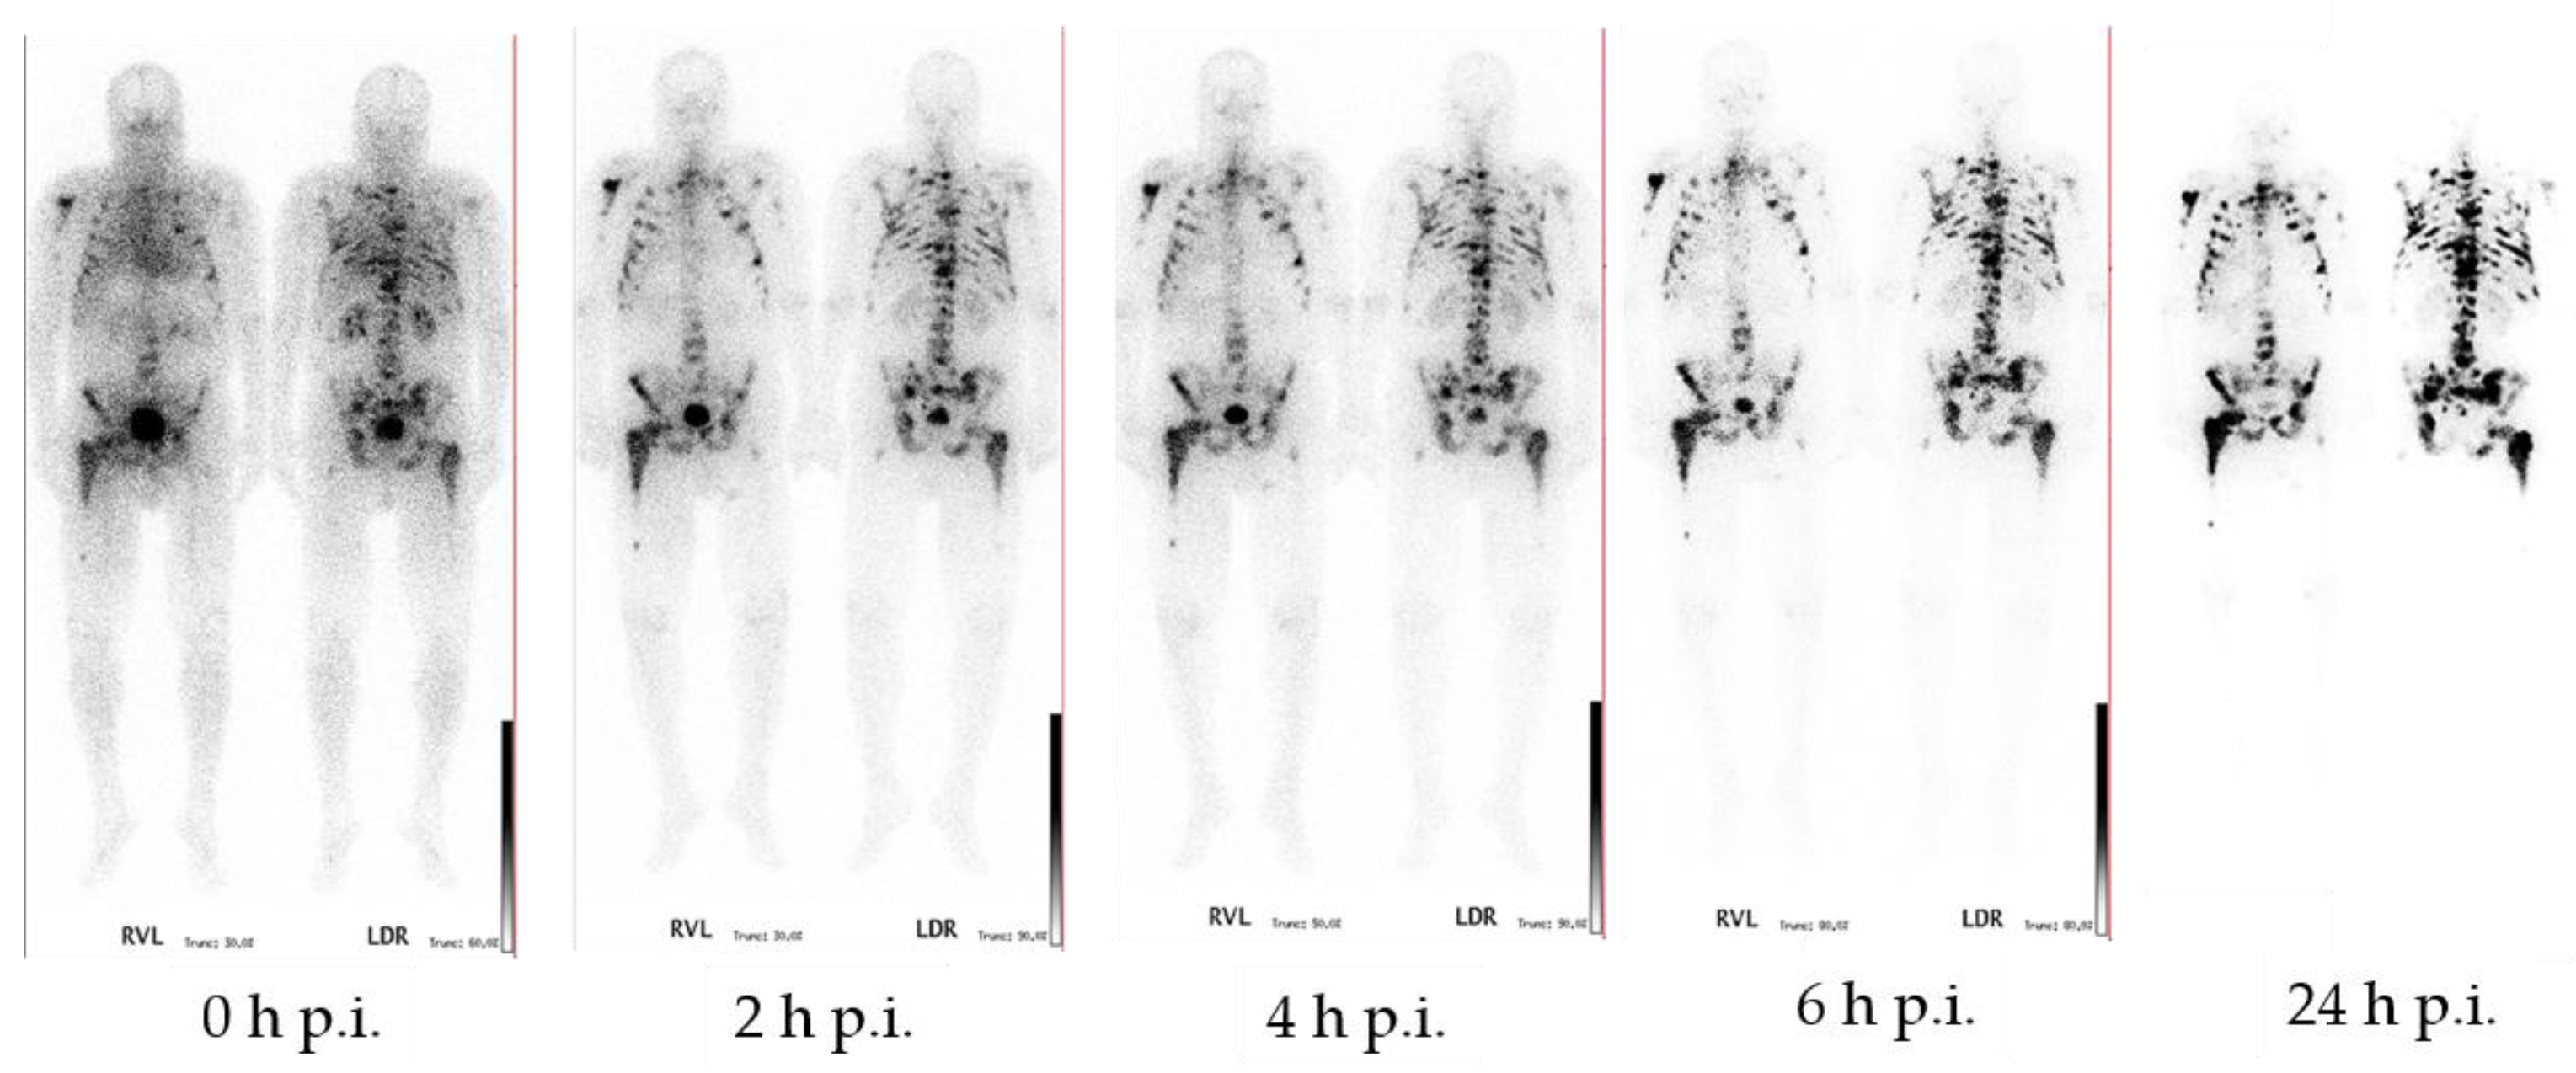

- Fellner, M.; Biesalski, B.; Bausbacher, N.; Kubícek, V.; Hermann, P.; Rösch, F.; Thews, O. 68Ga-BPAMD: PET-imaging of bone metastases with a generator based positron emitter. Nucl. Med. Biol. 2012, 39, 993–999. [Google Scholar] [CrossRef]

- Fellner, M.; Baum, R.P.; Kubíček, V.; Hermann, P.; Lukeš, I.; Prasad, V.; Rösch, F. PET/CT imaging of osteoblastic bone metastases with 68Ga-bisphosphonates: First human study. Eur. J. Nucl. Med. Mol. Imaging 2010, 37, 834. [Google Scholar] [CrossRef]